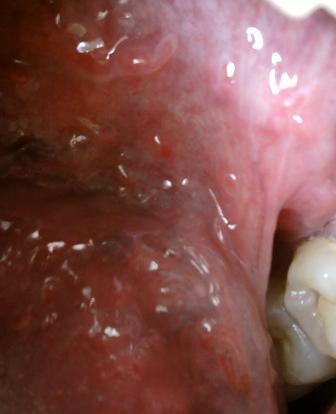

尖锐湿疣会不会再度交叉感染尖锐湿疣是病毒性疾病,病原体是人类乳头瘤病毒,而且病毒一般通常会通过以下几种途径传染。直接接触传染,间接接触传染以及母婴传染。因此如果是已婚的一方患病之后,首先应该禁止性生活,其次应该坚持夫妻同治,最后则要注意个人卫生,以免交叉感染,不利于疾病的治疗和恢复。